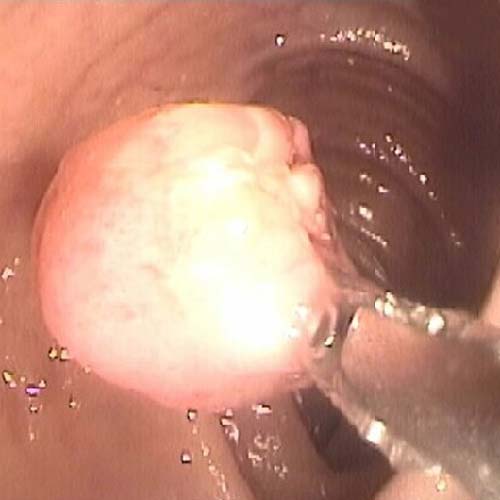

Procedimiento ambulatorio para detectar hemorragias digestivas, extirpación de pólipos, enfermedad de la vía biliar, extracción de cálculos, patología de colon o intestino delgado.

Procedimientos para visualizar el colon, tanto lumen como la mucosa, para tomar biopias o efectuar extirpación de pólipo, dilataciones, detención de un sangramiento y otras.

mediante una endoscopía digestiva alta permite observar directamente el estómago para detectar lesiones, tomar biopsias y confirmar o descartar cáncer de esófago, estomago y colon.